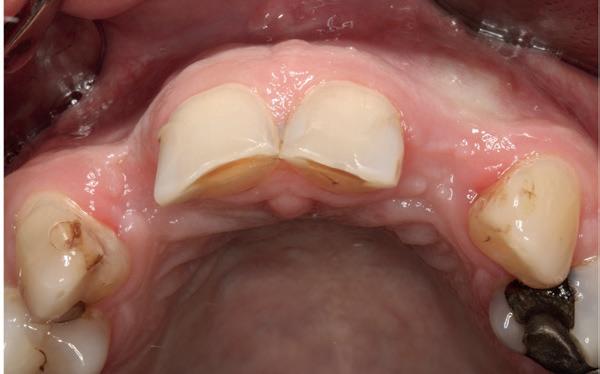

Esthetiek in de tandheelkunde, met name in het front, is een samenspel tussen de roze zachte weefsels en de witte harde weefsels. In het Engels wordt dit ook wel aangeduid met “pink and white esthetics”, waarbij het verkrijgen van correcte pink esthetics over het algemeen een grotere uitdaging vormt dan de white esthetics. Deze roze esthetiek is vooral van belang bij gebitselementen waarbij sprake is van recessie (het terugtrekken van de gingivalijn, waardoor de radix en een langere tand zichtbaar worden). De situatie wordt nog uitdagender wanneer een tand of kies niet is aangelegd, of in het verleden is verwijderd. Het element zorgt er immers voor dat de gingiva rondom de natuurlijke kroon ligt en dat er voldoende weefseldikte rondom deze kroon aanwezig is. Als het element ontbreekt, groeit het alveolaire bot dicht, omdat er geen radix meer is, en daarmee ook de mucosa (wanneer er geen element meer aanwezig is, spreken we niet meer van gingiva maar van mucosa), die dan afgevlakt is. De papillen tussen de afwezige elementen vlakken dan ook af.

Om één of meer afwezige elementen te herstellen bij een vaste voorziening, kan er een etsbrug of kunnen er implantaten worden geplaatst. De esthetiek valt of staat hierbij met de aanvulling van de zachte weefsels, zowel in de vorm van verbreding hiervan als het creëren van een zogenoemd emergence profile –dat wil zeggen dat de tand op een natuurlijk ogende wijze vanuit het tandvlees tevoorschijn moet komen.

18. Etsbrug frontbeeld

19. Etsbrug palatinaal